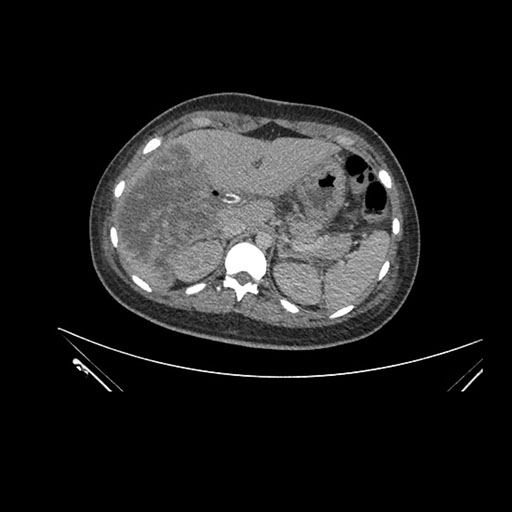

Imaging Analysis

Look through the patient's CT scan to identify any areas of concern for the necessary procedure.

Axial Arterial

Based on initial findings, which issue(s) would you be most concerned about?